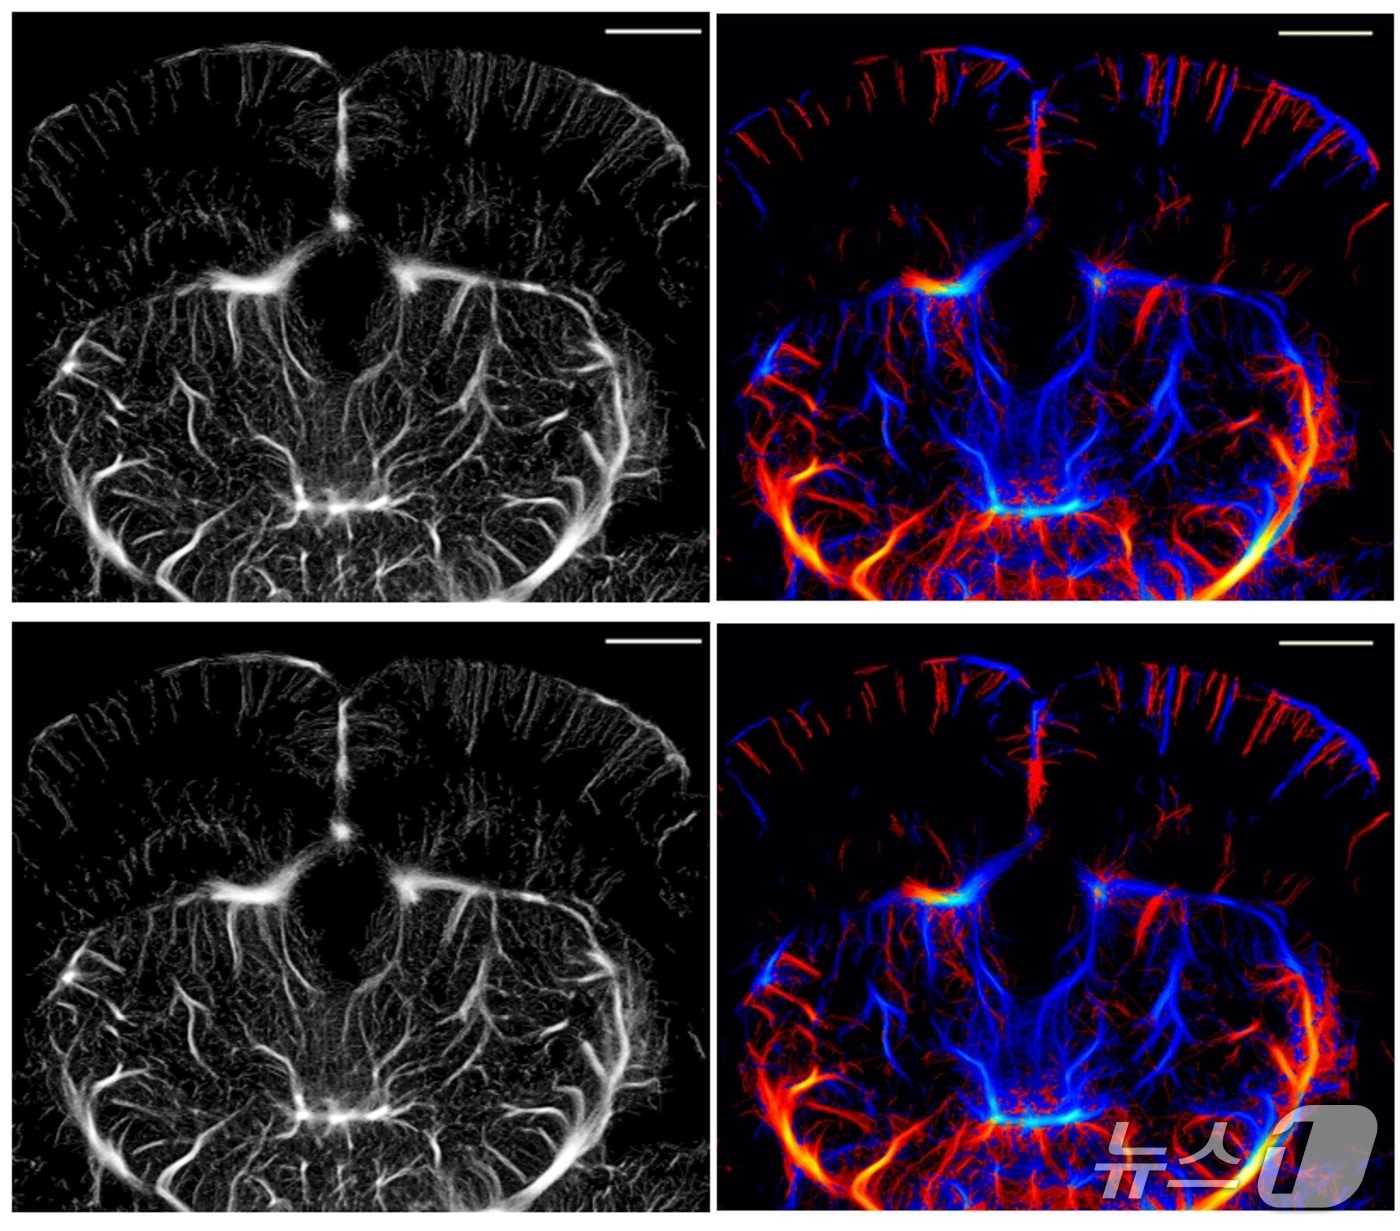

(대구=뉴스1) 이재춘 기자 = 대구경북과학기술원(DGIST)는 18일 초음파 국소화 현미경(ULM)의 효율성을 크게 높여 적은 데이터로도 미세혈관을 선명하게 볼 수 있는 기술을 개발했다고 밝혔다.

로봇·기계전자공학과 유재석 교수와 뇌과학과 현정호 교수 연구팀이 개발한 기술은 초음파 신호 중 핵심 정보만 남기고 불필요한 데이터를 과감히 줄이는 'ULM-Lite' 기법이다.

기존 초음파 장비를 그대로 쓰면서도 데이터를 3분의 1로 줄여 화질은 기존과 거의 같고 별도의 장비 교체 없이 적용할 수 있으며 영상 처리 속도는 30%가량 빠른 것이 특징이다.

또 수술이나 형광물질 없이 비침습적으로 뇌 전체를 선명하게 볼 수 있어 뇌 연구와 질환 진단의 효율성을 크게 높인 것으로 평가된다.